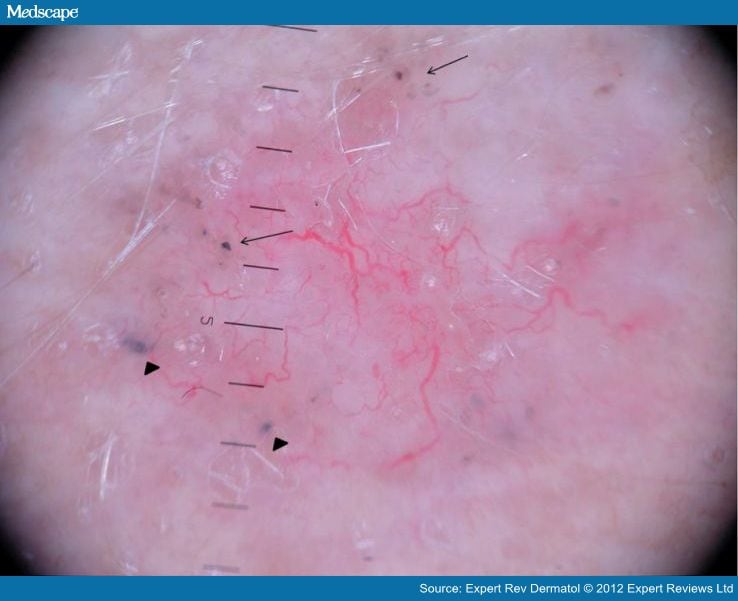

Dermoscopy Distinguishing Malignant Tumors From Benign Spoke Wheel Dermoscopy Spoke wheel areas are also known as radial projections joined at a central hub and are formed by nests and proliferation of pigmented basal cell. There are specific features that help to distinguish these. Dermoscopy is useful to distinguish pigmented basal cell carcinoma from other pigmented lesions. Dermoscopy improves diagnostic accuracy for bccs, helps differentiate bccs from other neoplastic and. Spoke Wheel Dermoscopy.